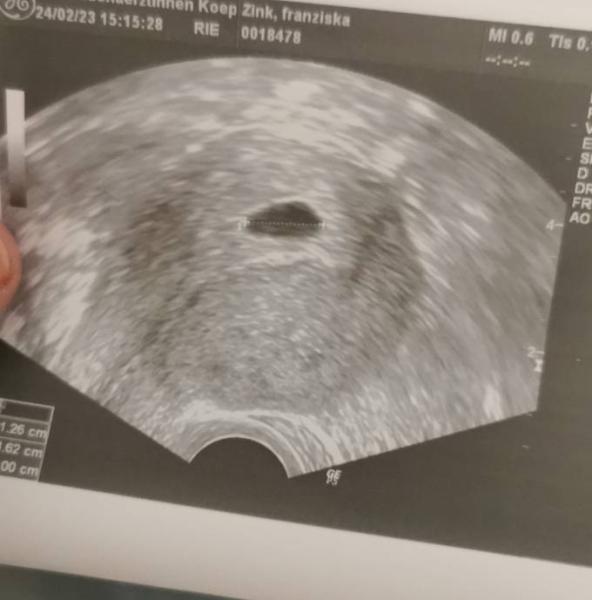

Hallo ihr Lieben, Ich habe mich am 7.2. positiv getestet. Hatte dann am 10.2.eh RoutineKontrolle bei meiner Frauenärztin wo ich das natürlich direkt ansprach. Beim Ultraschall war nur eine ideal aufgebaute Schleimhaut zu sehen. Gestern also 2 Wochen später war ich wieder zum Ultraschall. Fruchthöhle war zu sehen. Laut der Rechnung der Ärztin müsste ich gestern bei 7+2 gewesen sein. Entstanden ist das kleine Wunder am 15.01. Jetzt habe ich am Dienstag wieder Kontrolle weil die meinte es müsste dann wenigstens ein Dottersack zu sehen sein. Sie klärte Mich auch gleich, WENN Dienstag nichts zu sehen seie ich Tabletten bekomme um es zu beenden. Sie sagte aber im selben Atemzug ich solle mir keine Sorgen machen, es könnte auch am US Gerät liegen aber wirklich Mühe gegeben hat sie sich auch nicht. Ich hänge das Bild mal an. Ich persönlich sehe da was. Ganz oben in der Fruchthöhle. Hat noch einer ähnliche Erfahrungen? Ich werde hier verrückt Mein Mann hatte letztens Jahr Hodenkrebs und es war gesagt das er eigentlich gar nicht könnte. Wir haben so Angst

Bild zu Fruchthöhle ohne Inhalt - Schwanger - wer noch? Rund um die Schwangerschaft

Ich sehe ganz klar einen Inhalt in der Fruchthöhle. Es gibt ja auch sogenannte Eckenhocker...wäre super wenn du uns am Dienstag berichtest. Ich denke das alles super ist ! Wie ist denn der Hcg wert?

RegenbogenBaby, siehst du das gleiche wie ich? Bestätige mich doch bitte das ich nicht komplett bekloppt bin Meine Ärztin hat noch gar kein HCG gemessen. Keine Blutabnahme nix. Nur 2 mal US

Du bist ganz und garnicht bescheuert ich sehe das kleine Mäuschen:) ich hab bereits 2 Kinder und bei mir sah es auch so aus (: meine 2 werden bald 6 und 8 bitte berichte doch am Dienstag

Hallo, es gibt ja zwei Pünktchen auf dem Bild, oben und unten, und das spricht für einen normalen Ultraschallschatten. Ich würde mich aber auch nicht zum Abbruch drängen lassen. Man muss allerdings sagen: Bis der Körper eine sog. Missed Abortion (verhaltene Fehlgeburt, oft mit einem leeren „Windei“) von selbst abstößt, kann es bis zum Ende der ersten drei Monate oder sogar länger dauern. Weil das für die Frau sehr belastend ist (man ist schwanger, weiß aber wochenlang, dass es nichts mehr wird), schlägt der Arzt meist doch einen hormonellen Abbruch oder auch eine Ausschabung/Absaugung vor. Ich selbst habe damals auch noch zwei Wochen gewartet, bis ich selbst (!) völlig sicher war, dass es nichts mehr wird. In der 9. SSW hatte ich dann eine AS (10-Minuten-OP, geht auch ambulant). Ich drücke sehr, sehr feste die Daumen, dass noch etwas kommt! Wenn du magst, update uns doch mal. LG

Hej Frudoo. Ich hatte auch mal so ein Bildchen. Meine dritte Schwangerschaft sah bei 7+2 genauso aus, es war ein echter Eckenhocker. Tja, jetzt ist er 7 Jahre alt und freut sich auf die kleine Schwester, die im April kommt. Also, einfach den Termin am Dienstag abwarten, entspannen - es kommt so, wie es kommt. Schönes Wochenende!